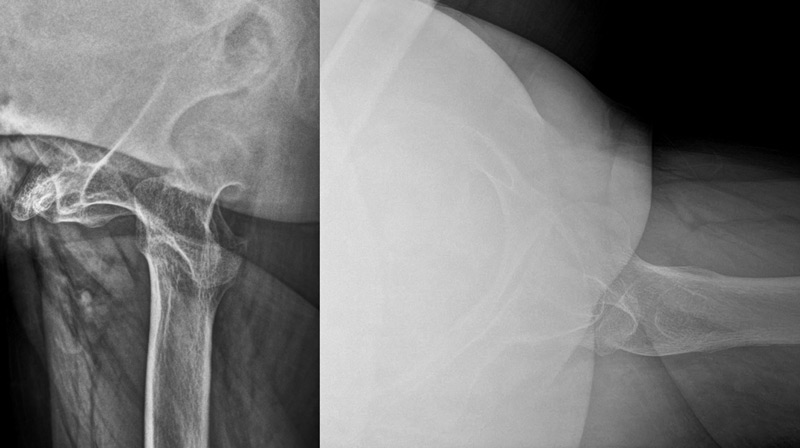

Pre-operative X-rays and CT-scan

Management of a hip dysplasia in a middle-aged woman:  Pre-operative X-rays and CT-scan

How would you grade this dysplasia?

• ✔️Crowe IV

How would you manage this condition?

• ✔️Hip replacement with Subtrochanteric osteotomy